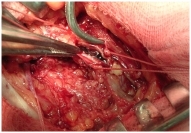

• 3. как выглядит тромбоз

Коварные тромбы прячутся в наших венах и могут проявляться в виде симптомов, а могут оставаться незамеченными. То, с чем я сталкиваюсь на приеме представлено здесь. Про интересные случаи из моей практики и результаты моих операций смотри ниже.